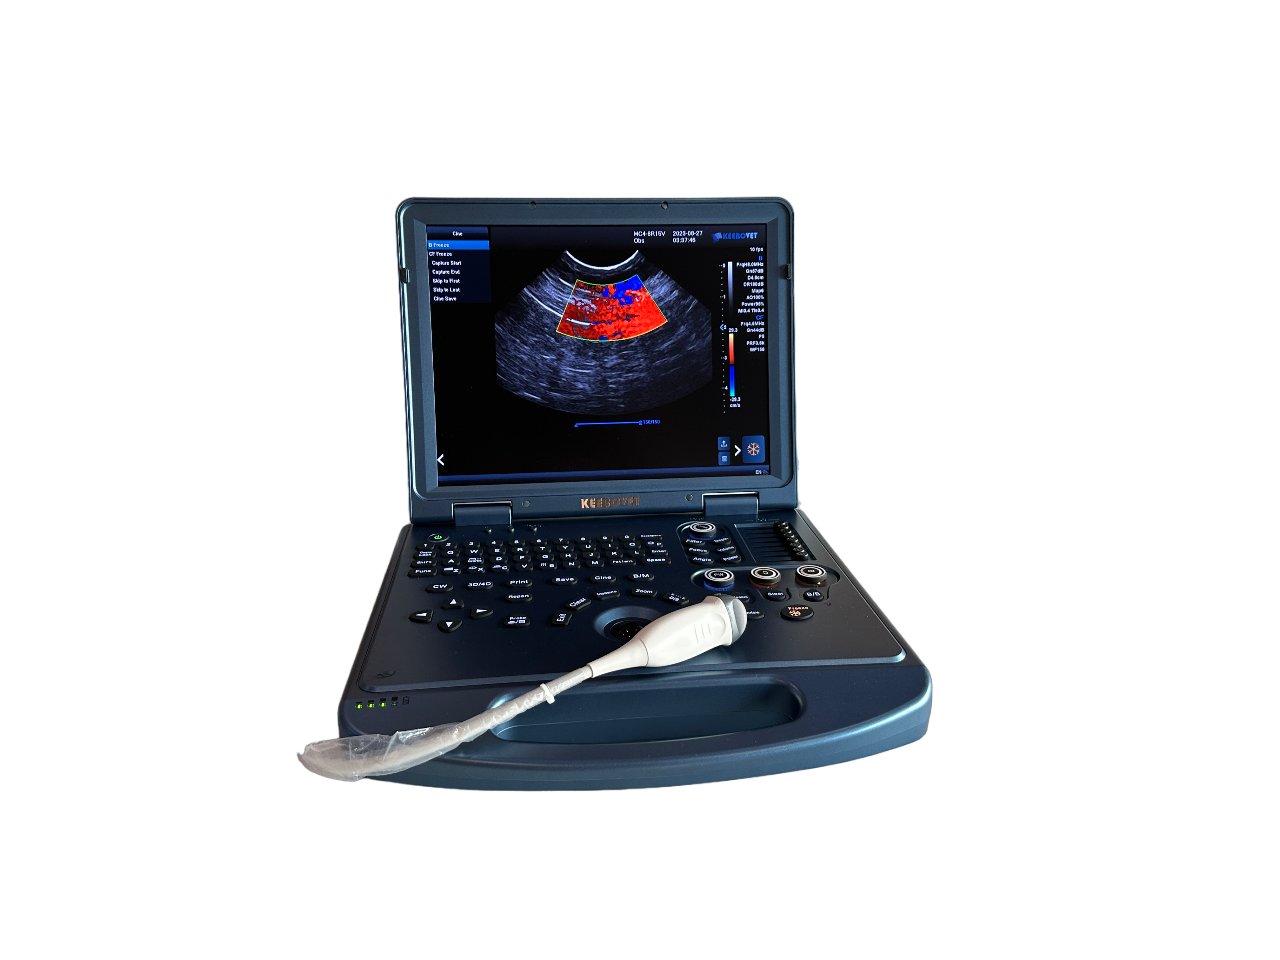

ECO-17Vet High end equine Ultrasound with Rectal Probe 4-12MHZ

High quality laptop Ultrasound

ECO17Vet High end Equine ultrasound with Top image quality.

1. Highly integrated hardware module with a lightweight body taking into account high-quality images, which provides great convenience for diagnosis.

4. Lightweight body and high quality images, built-in high-capacity lithium battery, support real-time three-dimensional imaging function.

Ultrasound Scanner Operation System:Windows8

Monitor: ≥ 15 inches